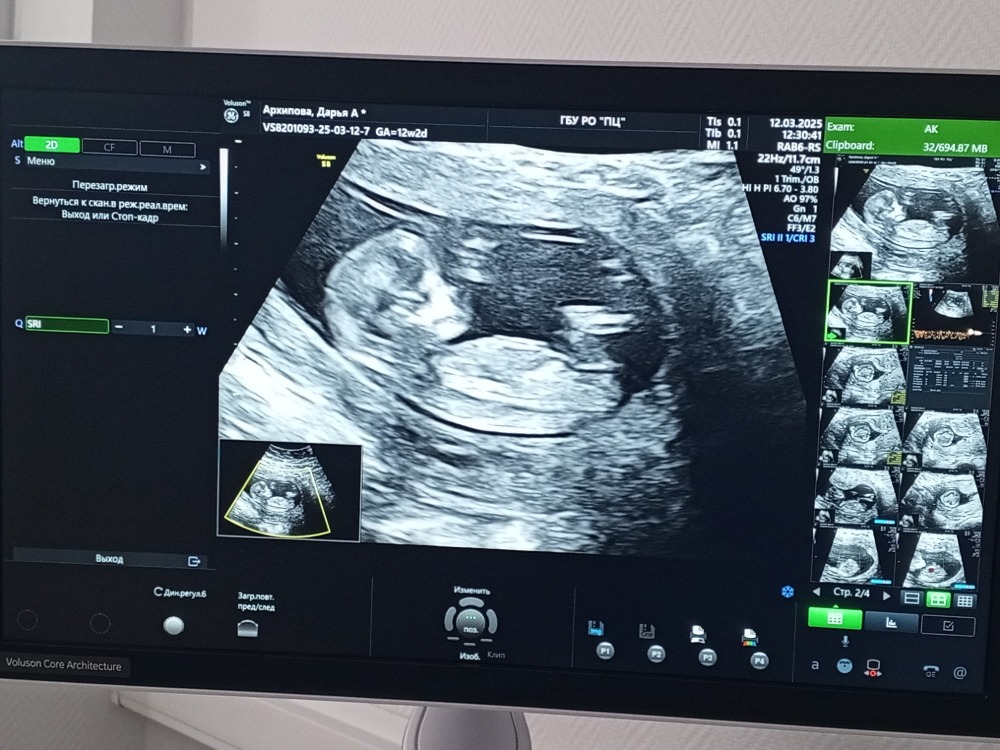

Сегодня прошла первый скрининг, срок 12н2д, последнее узи было в январе и очень волновалась 🙈 но, сказали что все отлично с малышом😻предположительно сказали девчушка🤗

12.03.2025